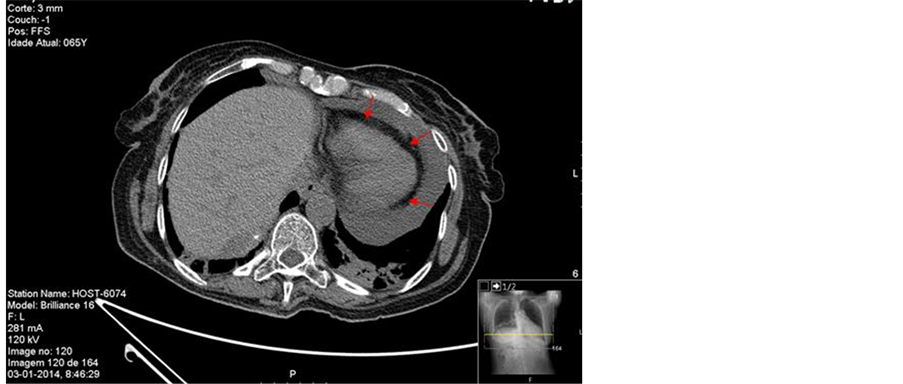

trophilia 80% and elevated CRP 11.5 mg/dL). Electrocardiogram presented with sinus tachycardia and low voltage. Chest radiograph revealed an increased cardiothoracic ratio, mediastinal widening and opacity in the middle lobe of the right lung (Figure 1).

Thoracic computed tomography (CT) scans showed a heterogeneous anterior mediastinal lesion with areas of central necrosis, necrotic nodular lesion of the pleura in relation to the right costophrenic angle and significant pericardial effusion. It also presented with extensive areas of lung consolidation with air bronchogram compatible with bilateral basal pneumonia and associated parapneumonic left pleural effusion (Figure 2).

Figure 1. Chest radiograph showed increased cardiothoracic ratio (>0.5), mediastinal widening, hypotransparent opacity in the middle right pulmonary lobe with dimensions of 41 × 28 mm and elevation of the right diaphragmatic dome.

Figure 2. (a) Thoracic computed tomography revealed significant pericardial effusion (arrows); (b) (c) Thoracic computed tomography showed a nodular mass measuring 28.6 × 25.5 mm, with irregular borders in the anterior mediastinum, heterogeneous density, areas of coarse calcification and central areas of necrosis at its lower strand located in the right cardiophrenic angle.